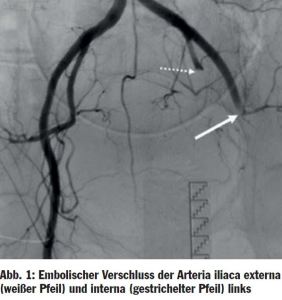

Ursächlich für eine akute kritische Ischämie kommen in erster Linie embolische oder thrombotische Gefäßverschlüsse in Betracht. Embolien verursachen mit 70–80% die große Mehrzahl der akuten Ischämien und sind insbesondere für die Mehrzahl der kompletten Ischämiesyndrome verantwortlich. Ein angiografisches Beispiel ist in Abbildung 1 dargestellt.

Abb_1